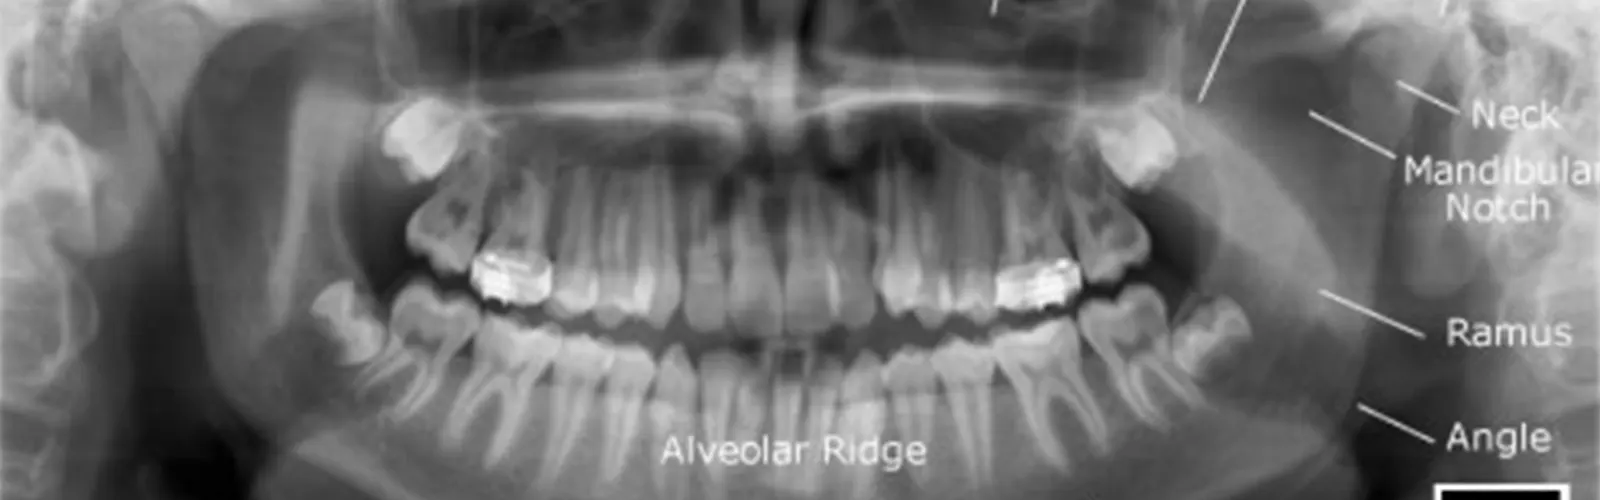

OPG (orthopantomogram) scan is not typically used as a primary tool for cancer detection, but it can be useful in detecting certain types of cancers that affect the oral and maxillofacial region.

An OPG scan can reveal abnormalities in the jawbone, such as cysts or tumors, which can be an indication of cancer. For example, an OPG scan can detect the presence of odontogenic tumors, which are growths that originate from the cells that form teeth or from the tissues surrounding teeth. These tumors can be benign or malignant and may require further investigation, such as a biopsy or additional imaging tests.

In addition, an OPG scan can also help detect metastatic cancer that has spread to the jawbone from other parts of the body. Metastatic cancer in the jawbone is often an indication of advanced cancer, and additional tests may be needed to determine the origin and stage of the cancer.